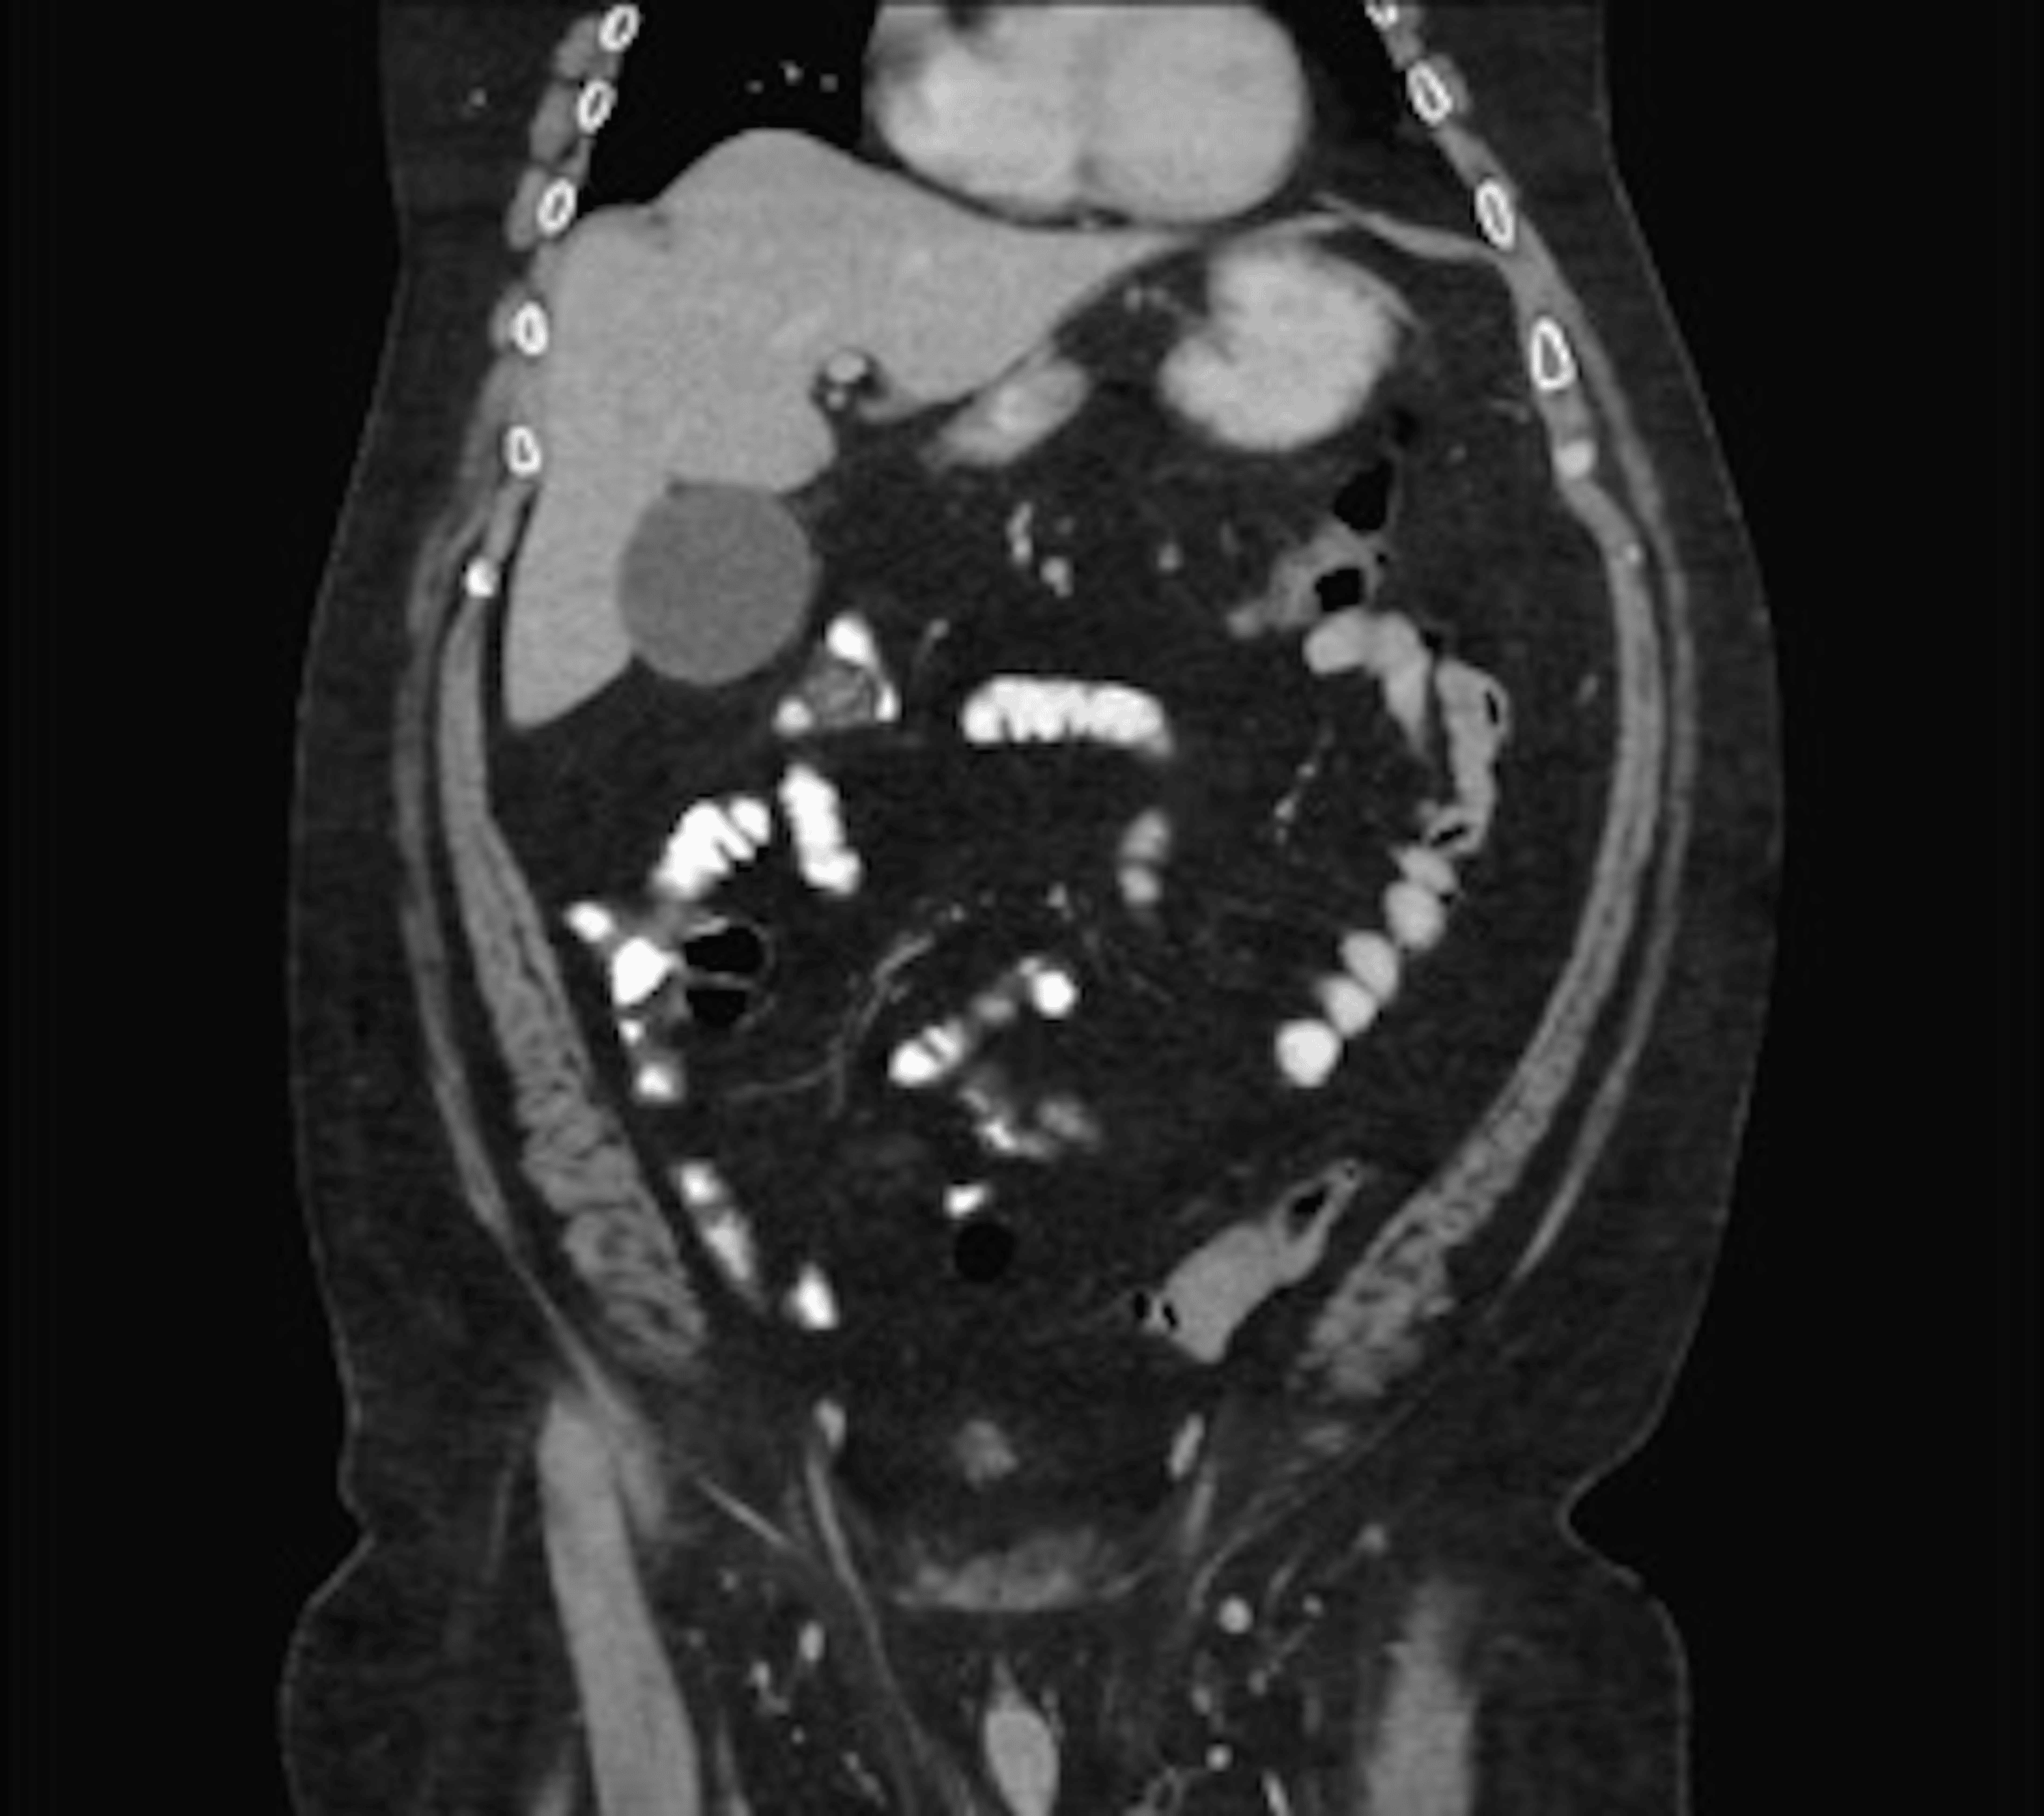

Concurrent large bowel obstruction secondary to idiopathic Endoscopic Decompression Gastric Volvulus Although the exact role of endoscopy is still not entirely clear in treating volvulus, endoscopic techniques for volvulus. If there is acute gastric distention due to gastric volvulus, an immediate gastric decompression at the bedside required (with a. Acute gastric volvulus associated with wandering spleen in an adult treated laparoscopically after endoscopic reduction: The diagnosis of volvulus based on radiographs. Endoscopic Decompression Gastric Volvulus.

Figure 1 from Acute gastric volvulusendoscopic derotation. Semantic Endoscopic Decompression Gastric Volvulus Acute gastric volvulus associated with wandering spleen in an adult treated laparoscopically after endoscopic reduction: Patients who present with acute gastric volvulus without evidence of critical illness (ie gastric necrosis, ischemia, or sepsis) can be managed. The diagnosis of volvulus based on radiographs was supported by endoscopy that revealed abnormal gastric anatomy with twisting of the gastric folds and difficulty. Endoscopic Decompression Gastric Volvulus.